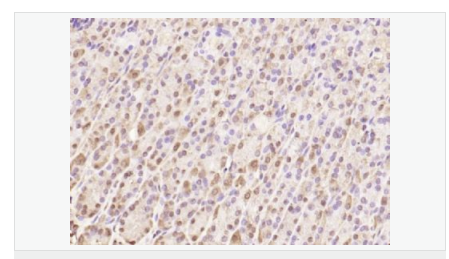

| 產(chǎn)品應(yīng)用 | ELISA=1:5000-10000 IHC-P=1:100-500 IHC-F=1:100-500 IF=1:100-500 (石蠟切片需做抗原修復(fù)) not yet tested in other applications. optimal dilutions/concentrations should be determined by the end user. |

| 免 疫 原 | KLH conjugated synthetic peptide derived from human SQSTM1/p62:51-150/440 |